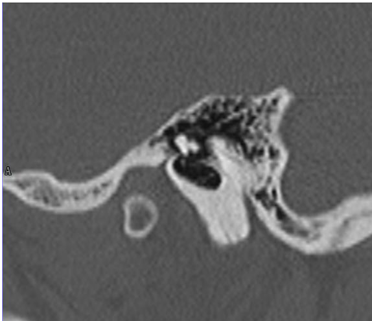

The patient was M.E.M., 50years old, ASA1, female with chronic ear disease with polyposis of the right ear; with moderate type I (50dB HL) conductive hearing loss. A CT scan is presented on Figure 1 & 2. The treatment was initiated after written informed consent, with amoxicillin and clavulanic acid (875 m+ 125 mg) in a form of ½ pill twice per day and prednisolone 5mg /day.

Figure 1 MEM, 50 yrs female, OMC with polyps, R ear before treatment.

Figure 2 MEM, 50 yrs female, OMC wit polyps, R ear before treatment.